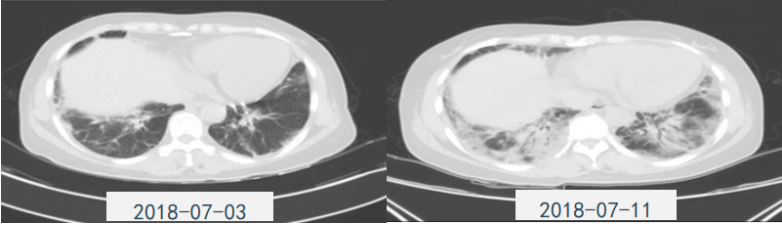

患者,女,50岁;活动后喘息20天,加重伴发热3天,2021年11月19日转入我院。入院胸部CT显示:双肺实变,磨玻璃影(图1)。11月24日复查胸部CT可见病变进展迅速(图2)。予患者气管插管机械通气、俯卧位等,呼吸衰竭未见改善。遂于11月25日启动VV-ECMO(转速2860 rpm,流量4.5 L/min,氧浓度100%)。追问病史:患者入院前1月有活动后气促症状,自觉全身不适,近2年有眼干、口干不适。进一步检查发现,ANA反应阳性(+),ANA核型为胞浆颗粒型(异常);抗SSA/Ro抗体阳性(++)、抗Ro-52抗体阳性(+++)。诊断:急性间质性肺炎(AIP);Ⅰ型呼吸衰竭;混合性结缔组织病。治疗:VV-ECMO+呼吸机辅助通气+俯卧位通气、激素(甲强龙80 mg×7天,60 mg×3天,40 mg qd)、免疫抑制剂(环磷酰胺400 mg qd×3天)、抗感染(哌拉西林他唑巴坦4.5 g q12h+莫西沙星0.4 g qd+氟康唑氯化钠注射液20 mg qd)、抗凝等。在随后的一段时间内,患者影像学改善不明显(图3)。直至12月20日,复查胸部CT可见患者肺部病变较前明显吸收(图4)。2021年12月31日VV-ECMO撤机后,继续气切呼吸机辅助通气,甲强龙40 mg qd抗炎治疗,继续抗感染治疗,2022年1月7日脱机,1月21日气管封管,1月26日出院。后续治疗:强的松25 mg qd,环磷酰胺600 mg q2w×4次,序贯吗替麦考酚酯0.5 g bid。重症间质性肺疾病(ILD)在诊断方面需要考虑以下问题:是ILD吗?是哪种ILD?严重程度如何?在治疗方面,除了生命支持(呼吸支持重点)和病因治疗,并发症的处理也至关重要。重症ILD的诊断包括两方面,一方面是通过影像学、病史+临床表现、BALF-NGS、实验室检查、肺活检等对ILD进行诊断;另一方面涉及重症,患者多面临呼吸衰竭甚至多器官衰竭,因此时间更加紧迫。在ICU内最常见的重症ILD包括:特发性肺纤维化急性加重(AE-IPF)、自身免疫相关性ILD、肿瘤治疗相关性ILD、隐源性机化性肺炎(COP)、AIP、过敏性肺炎(HP)、急性嗜酸性粒细胞性肺炎(AEP)、药物相关ILD等。在影像学方面,最易导致重症的类型有弥漫性磨玻璃影和实变影。最常见的鉴别诊断就是重症肺部感染。表现为弥漫性磨玻璃影或实变影的ILD较为多见,例如:HP、嗜酸性粒细胞性肺炎(EP)、结缔组织病相关间质性肺病(CTD-ILD)、非特异性间质性肺炎(NSIP)、脱屑性间质性肺炎(DIP)、淋巴细胞性间质性肺炎(LIP)、机化性肺炎(OP)、AE-IPF、肺泡蛋白沉积症(PAP)、肺泡微结石症、结节病、弥漫性肺泡出血综合征、肺水肿等。而很多感染性疾病影像学也可表现为磨玻璃影,例如:卡氏肺孢子菌肺炎(PCP)、病毒性肺炎、巨细胞病毒性肺炎、支原体肺炎。尽管如此,ILD也有部分影像学具有特征性,可以被识别。图5左表现为肺陷闭,也称为“猪头肉冻征”,这是典型的亚急性HP的影像学特征。图5右表现为弥漫性磨玻璃影,但以肺门向外扩展,外面有肺大泡,这是典型的PCP表现。临床上多见自身免疫性疾病导致的ILD,此类疾病也具有共同的特征,例如双肺弥漫,病理方面以NSIP或OP为主要特征。但也有部分患者可以出现弥漫性肺泡损伤(DAD)特征。如图6所示,左图为ANCA相关性血管炎,右图为MDA5相关性间质性肺病。因此,一定要警惕容易发生这种病理改变的自身免疫性疾病。